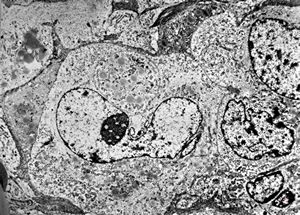

F,66y. | myositis